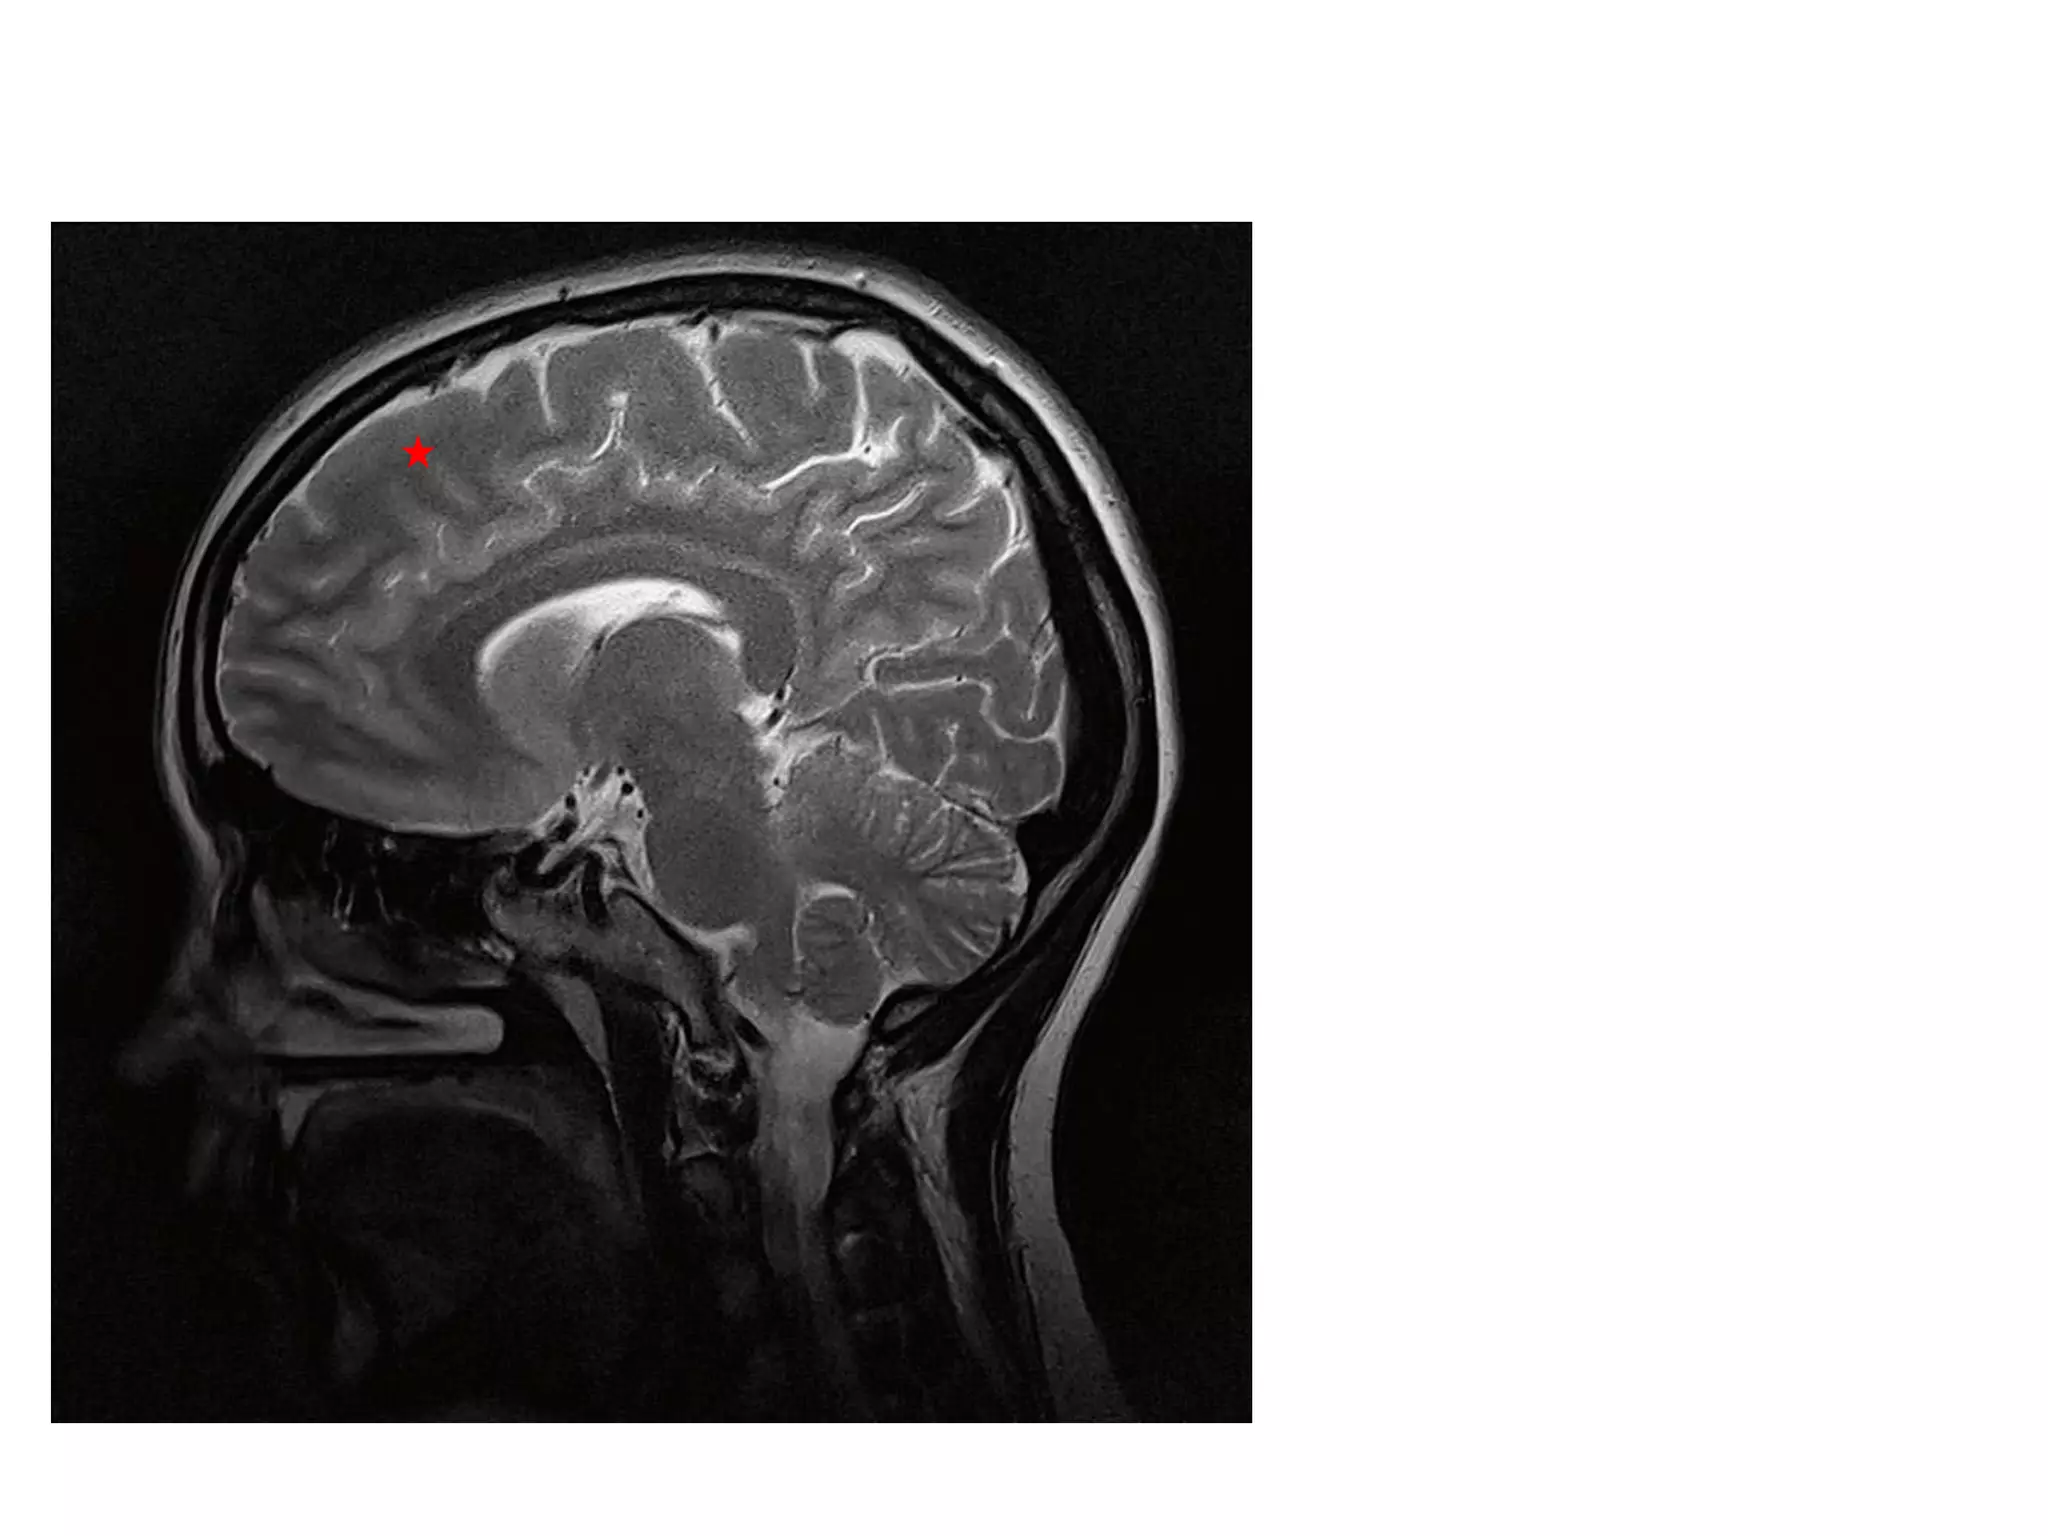

• Anatomy of cerebral hemispheres and mid brain – T1 W

MRI.

• Internal grey - white matter areas – T2 W MRI.

• In Cerebral hemispheres , white matter above the level of

lateral ventricles is called centrum semiovale

MEDIAL SAGGITAL :

By tracing cingulate sulcus to its posterior limit , where it

forms marginal sulcus.

LATERAL SAGGITAL

Into Inferior frontal gyrus, sylvian fissure forms Y shaped

sulcus . Behind it is precentral sulcus.